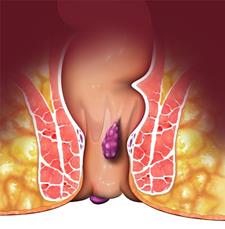

بواسیر خارجی یک نوع بیماری مقعدی است که در اثر فشار به روده ها بوجود می اید

بواسیر خارجی یا هموروئید خارجی زمانی ایجاد می شود که سیاه رگ های اطراف خارج مقعد گشاد یا شل می شوند. این بیماری با احساس فشار و درد در هنگام عمل دفع یا تمیز کردن ناحیه مقعد همراه است. طول دوره این بیماری نا مشخص است و بستگی به میزان شدت آن دارد. بواسیر خارجی کوچک بدون نیاز به درمان بهبود می یابد اما بواسیر خارجی بزرگتر به مدت زمان بیشتری برای بهبودی و درمان نیاز دارند.

• وجود لخته های خون؛ در صورت ایجاد لخته های خونی در رگ های خونی هموروئید سبب توقف جریان خون و ایجاد ترومبوز می شود که به این حالت ترومبوز هموروئید می گویند. بوسیر ترومبوزه به رنگ تیره آبی مایل به بنفش است و دردناک می باشد. لخته های خونی معمولا توسط بدن دفع می شود و درد آن بر طرف می شود. اما ممکن است در محل آن زائده های پوستی ایجاد شود که باید با جراحی برداشته شود.